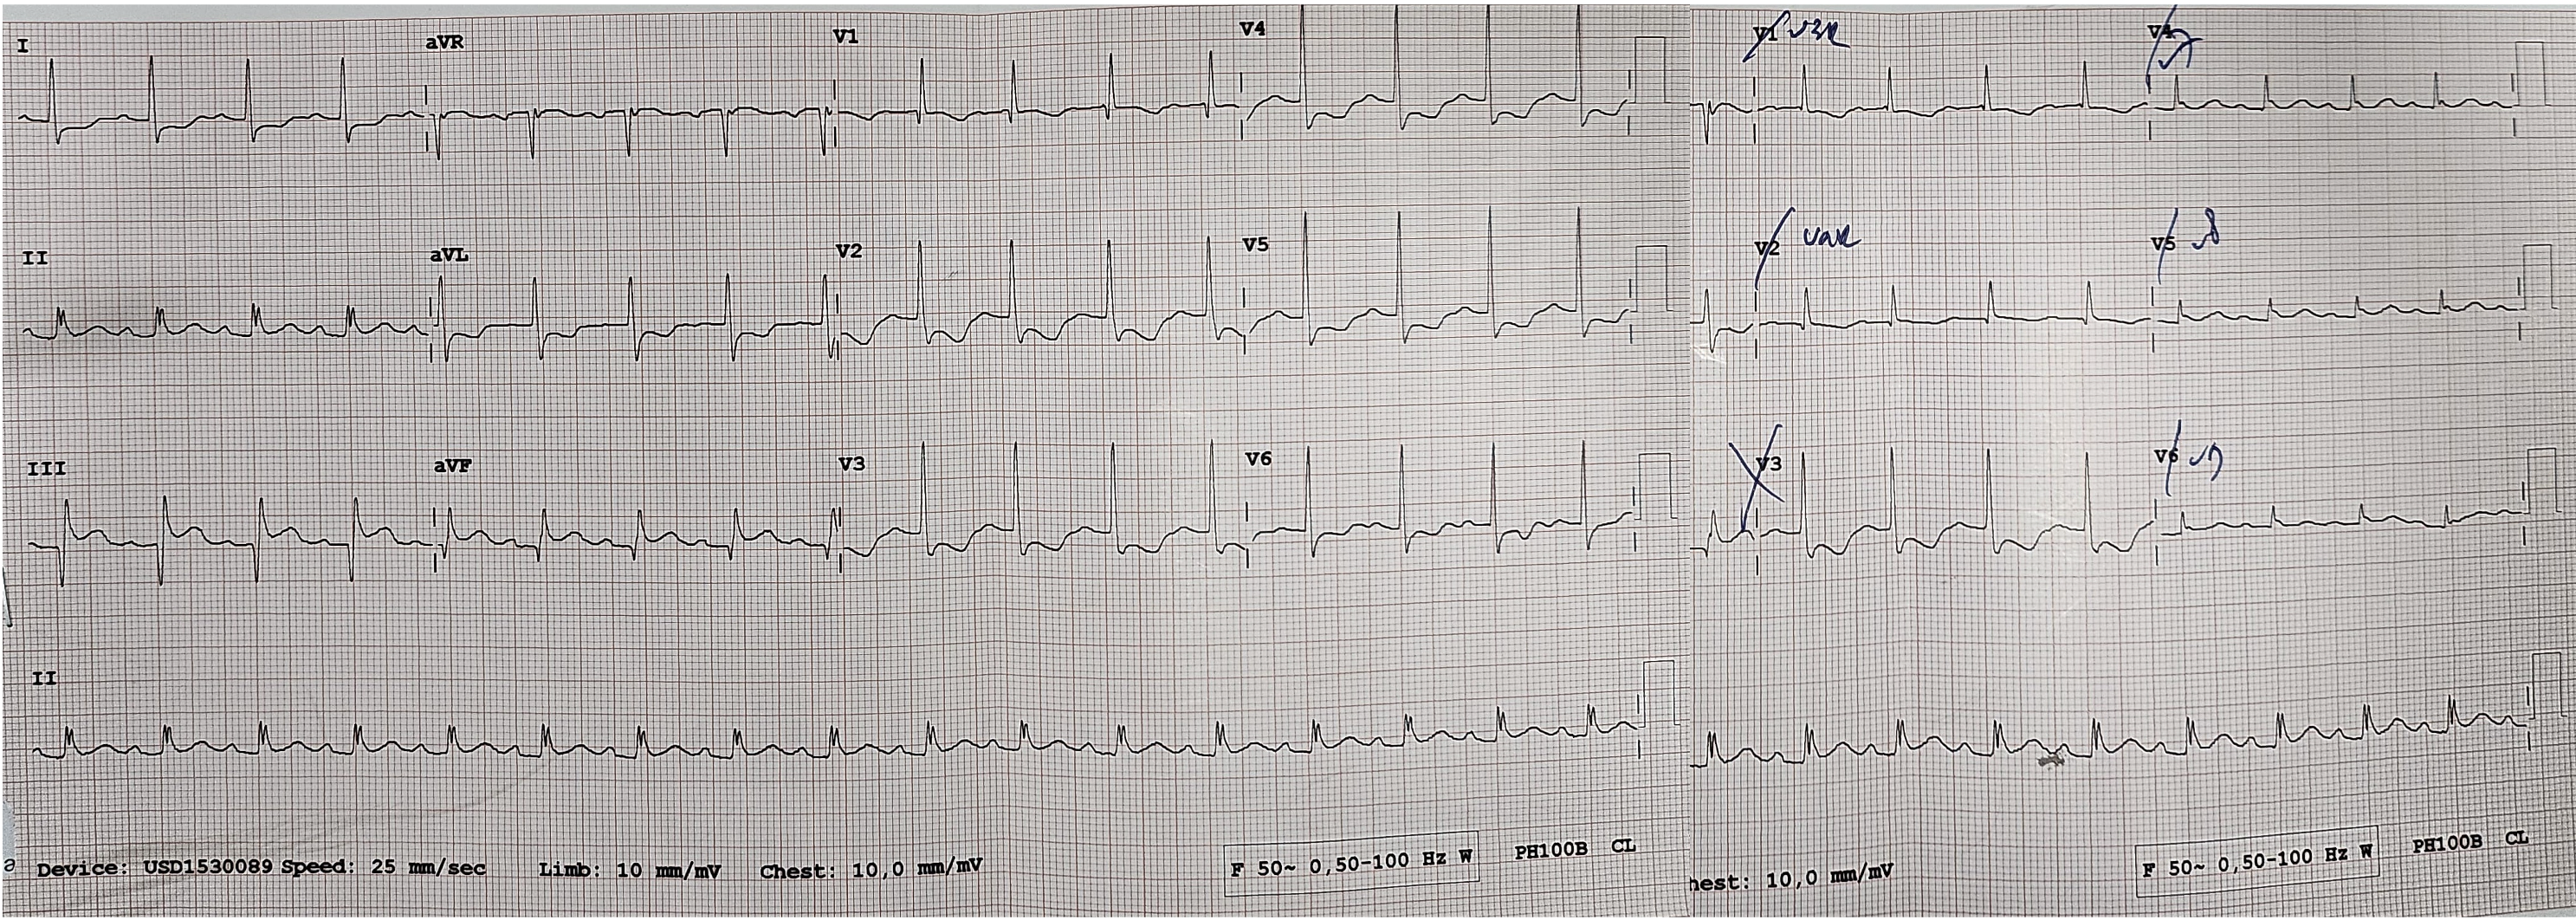

The electrocardiogram prior to catheterization procedure revealed sinus tachycardia with persistent ST-elevation and Q wave at lead III and AVF, ST depression at V4-V6, I, AVL. Echocardiography demonstrated good left ventricular function (LV EF 56%), reduced right ventricular function, global normokinetic and mild tricuspid regurgitation. Laboratory test result were unremarkable.